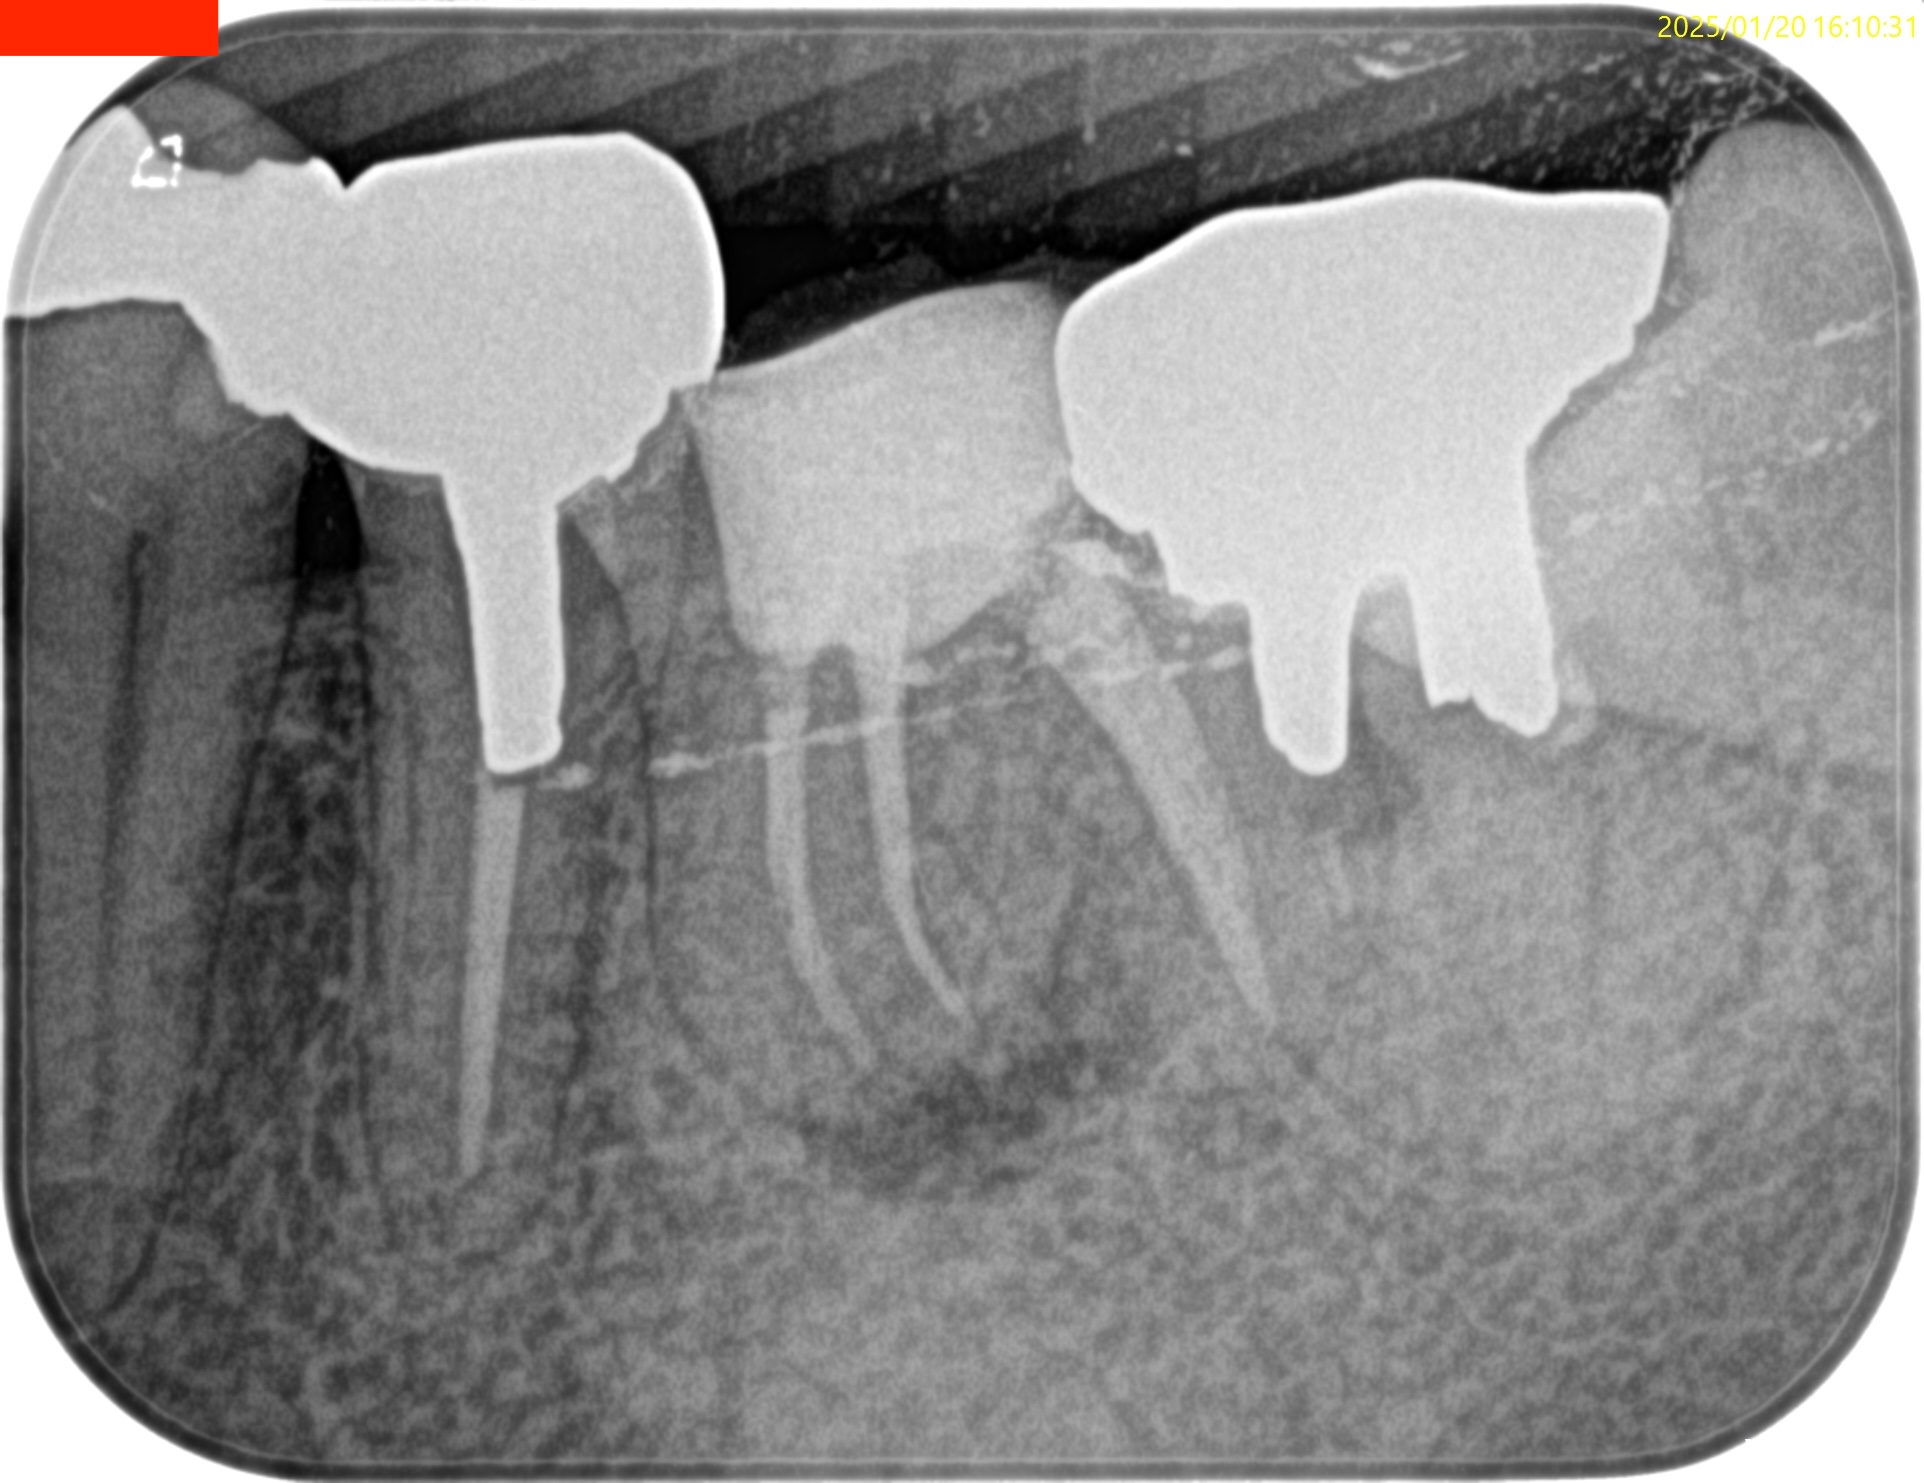

Pre-op PA(2025.1.10)

Pre-op CBCT(2025.1.10)

MB

ML

D

根尖病変があるのは近心根のみであるので近心根のみ再根管形成することにした。

その際は、

MBもMLも穿通させる必要があることがCBCTを見える絵にしていけばわかる。